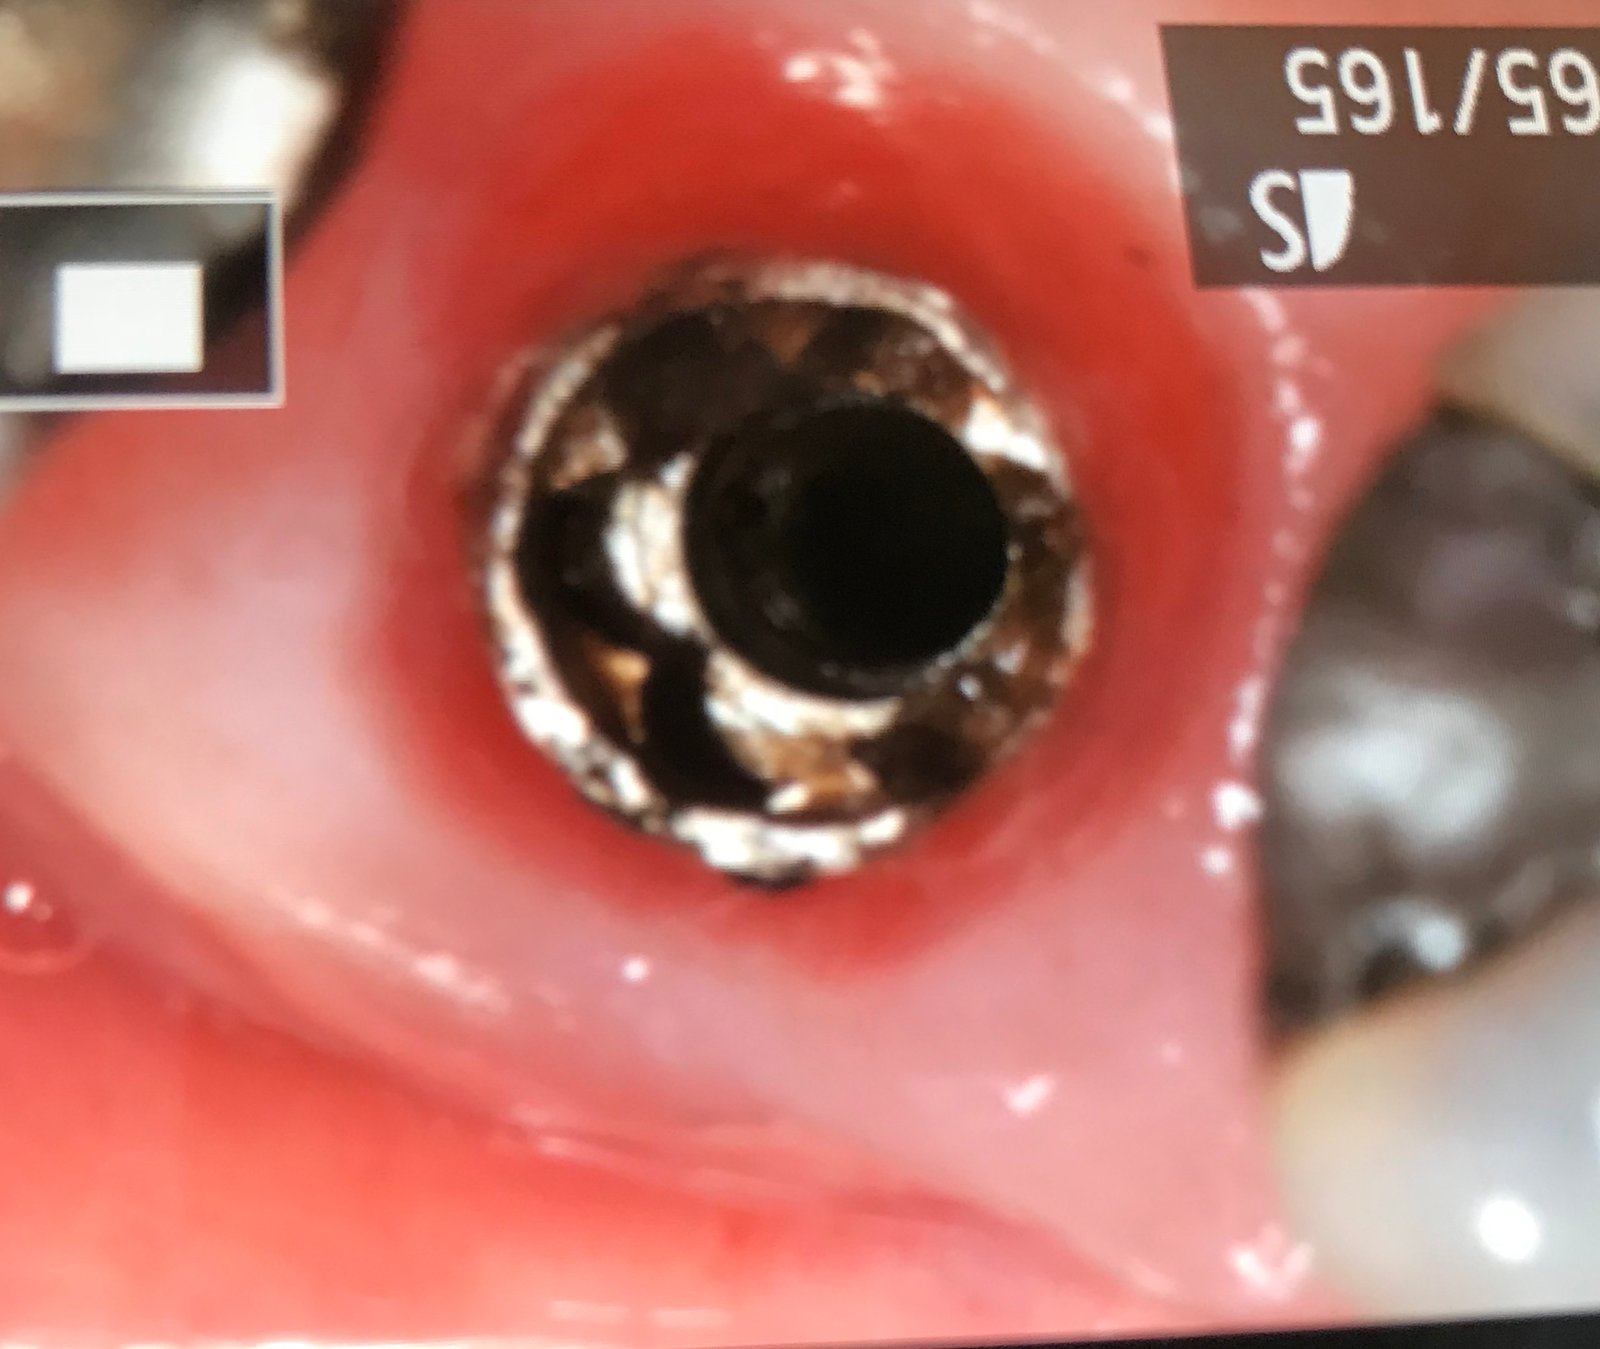

Al descubrir el acceso al tornillo es plano , no se que destornillador es.

Por favor a ver si alguno sabéis cual es el implante del 12. El paciente se lo colocó en otra clínica y han desaparecido. Conexión interna pero cuadrada (os mando [...]